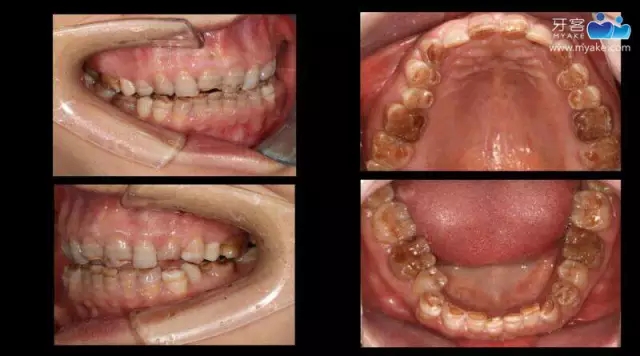

從DSD設(shè)計到瓷貼面實現(xiàn)(上)—李偉老師